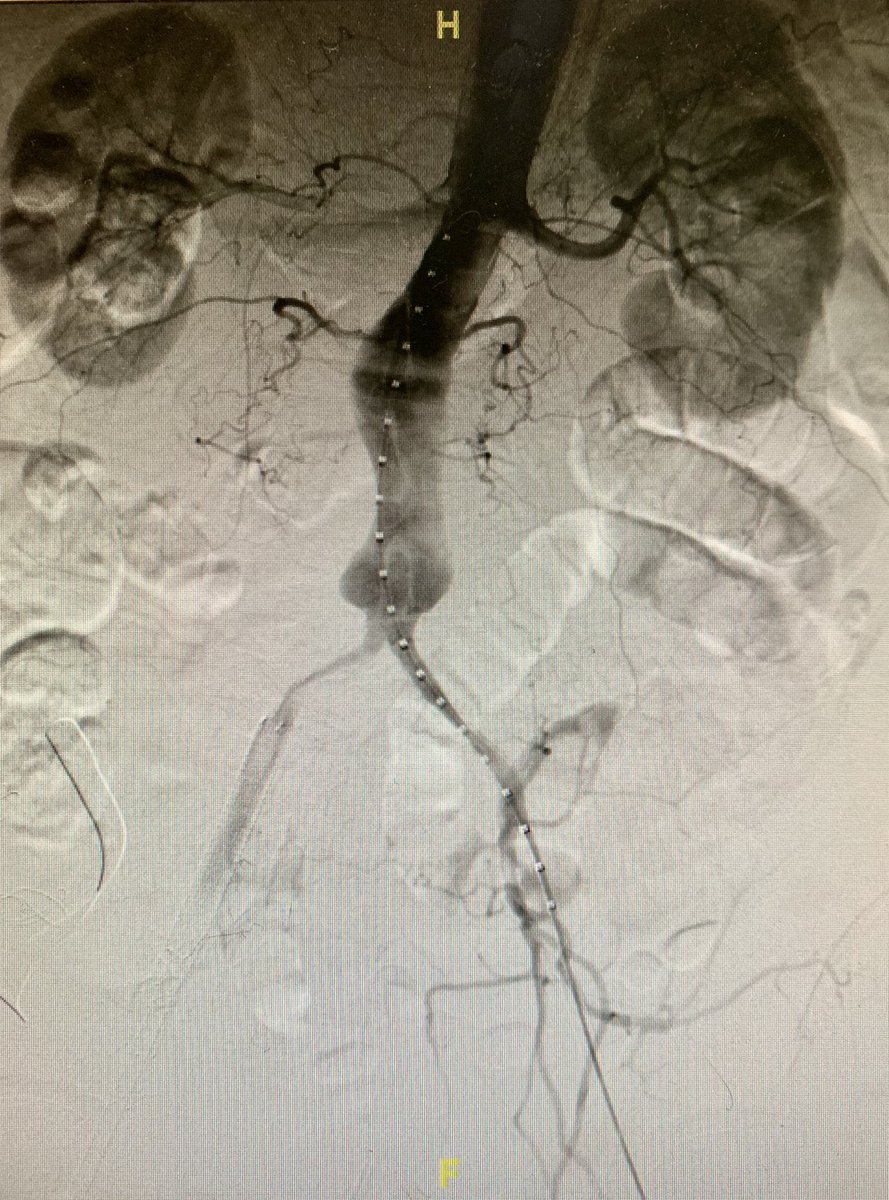

Successful fully percutaneous #EVAR for a 5.5 cm infra-renal abdominal aneurysm #AAA with mural thrombus through severely diseased iliac arteries. @GPAngioClub @ACVCPhila @jcgeorgemd @endologix @PennCardiology @PennCVFellows